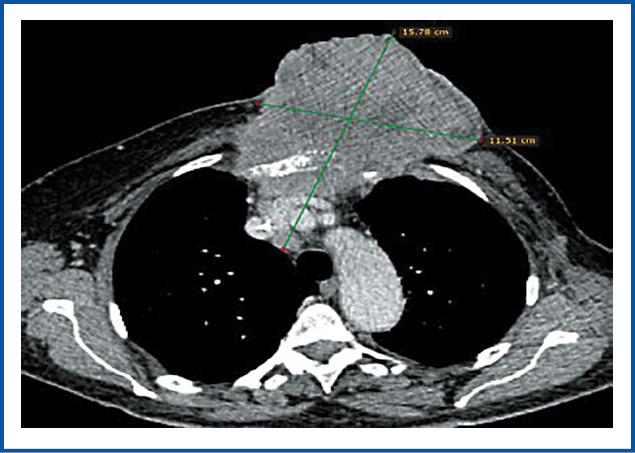

Положительный эффект зафиксирован к моменту окончания ЛТ в виде частичной регрессии первичной опухоли более 50% и отсутствия эпизодов кровотечения (рис. 4, 5, a).

Рис. 4. Картина КТ грудной клетки после ЛТ. Размеры опухолевых узлов обозначены зелеными линиями: a – вид грудной стенки на уровне ThV позвонка; b – вид грудной стенки на уровне ThIII позвонка.

Fig. 4. CT scan of the chest after RT. The dimensions of the tumor nodes are indicated by green lines: a – view of the chest wall at the level of the ThV vertebra; b – view of the chest wall at the level of the ThIII vertebra.